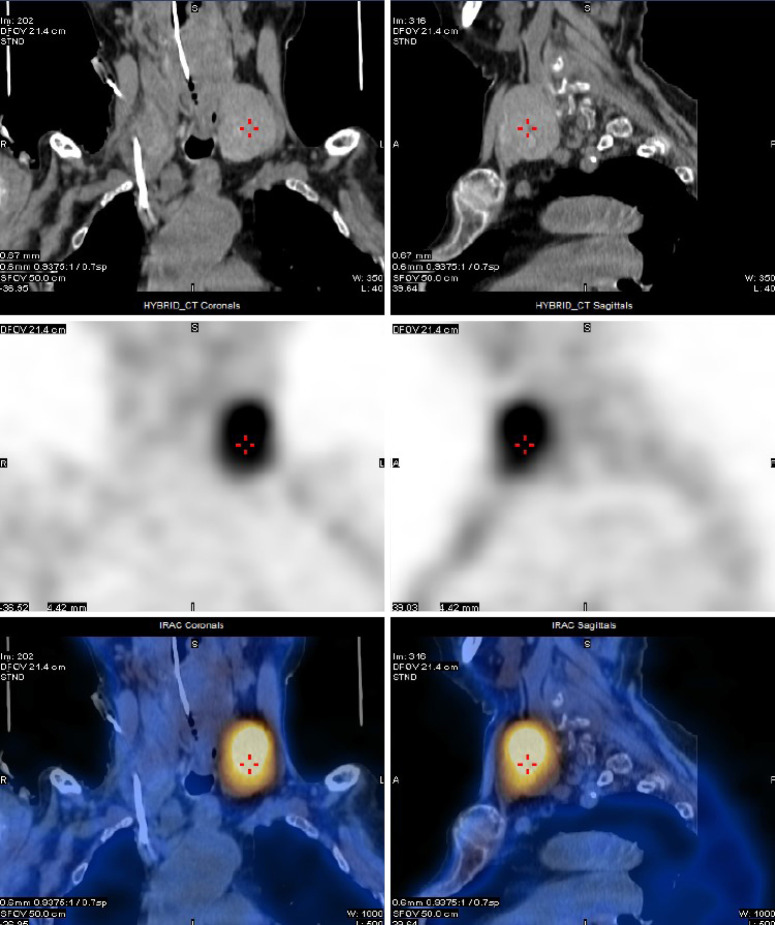

背景:甲状旁腺癌是一种罕见的内分泌恶性肿瘤。大多数病例为功能性甲状旁腺癌,而极少数为非功能性甲状旁腺癌。非功能性甲状旁腺癌患者的预后通常比功能性甲状旁腺癌患者差。这通常是由于非功能性甲状旁腺癌的隐匿性,通常导致较晚的发现和诊断。病例描述:2011年5月至2022年11月,浙江大学第一附属医院对6例诊断为甲状旁腺癌的患者进行了手术治疗。其中2名男性,4名女性,年龄从53岁到83岁不等。2例肿瘤位于右颈,4例肿瘤位于左颈。最小的肿瘤直径为2.5厘米,而最大的肿瘤直径为11.4厘米。2例为异常罕见的非功能性甲状旁腺癌,4例为功能性甲状旁腺癌。所有6名患者都接受了手术。病理类型包括主细胞型2例,混合细胞型2例,嗜氧细胞型1例,透明细胞型1例。随访时间为1 ~ 151个月。5名患者存活,1名患者死亡。无功能甲状旁腺癌患者均有复发和转移,Ki-67水平分别为30%和20%。相比之下,4例功能性甲状旁腺癌患者均无复发,1例Ki-67水平为20%,3例Ki-67水平为5%。结论:非功能性甲状旁腺癌患者预后不良可能反映了其生物学行为和较高的恶性潜能。Ki-67水平与甲状旁腺癌的恶性潜能呈正相关。这些推测仍然需要通过大规模的临床研究来验证。

Case description: Between May 2011 and November 2022, the First Affiliated Hospital of Zhejiang University conducted surgical treatment on six patients diagnosed with parathyroid carcinoma. Of these, two were male and four were female, with ages spanning from 53 to 83 years. The tumors were situated on the right neck in two cases and on the left neck in four cases. The smallest tumor measured 2.5 cm in diameter, whereas the largest measured 11.4 cm. Two cases were exceptionally rare nonfunctional parathyroid carcinomas, and four were functional parathyroid carcinomas. All six patients underwent surgery. Pathological types comprised the chief-cell type in two cases, the mixed-cell type in two cases, the oxyphil-cell type in one case, and the clear-cell type in one case. The follow-up duration ranged from 1 to 151 months. Five patients remained alive, while one patient died. Both patients with nonfunctional parathyroid carcinoma experienced recurrence and metastasis, with Ki-67 levels of 30% and 20%, respectively. In contrast, none of the four patients with functional parathyroid carcinoma recurred, with one case having a Ki-67 level of 20% and three cases with a Ki-67 level of 5%.